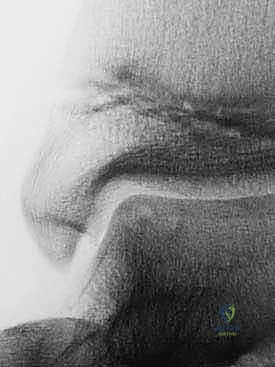

المرحلة الأولى: جراحة الحصاد (Harvesting) والتنظير

هذه المرحلة هي جراحة يوم واحد بسيطة، تُجرى تحت التخدير الموضعي أو العام باستخدام منظار الكاحل بتقنية 4K عالي الدقة.

1. الاستكشاف والتنظيف: يُدخل الدكتور هطيف الكاميرا الدقيقة لتقييم حجم الآفة بدقة، وتنظيف أي أنسجة تالفة أو أجسام حرة داخل المفصل.

2. أخذ الخزعة (Biopsy): يتم أخذ عينة صغيرة جداً من الغضروف السليم (بحجم حبة العدس أو أقل من 200-300 مليغرام) من منطقة غير حاملة للوزن في المفصل (Non-weight bearing area)، بحيث لا يؤثر أخذها على وظيفة الكاحل.